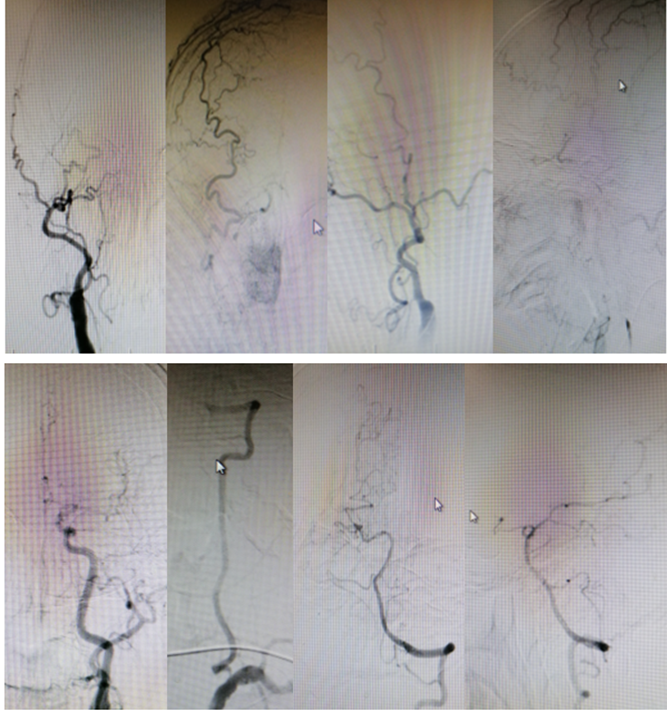

手术方案

病历夹什么径技·第151期|串联营病历夹:京广连营_https://www.jmylbn.com_新闻资讯_第55张

病历夹什么径技·第151期|串联营病历夹:京广连营_https://www.jmylbn.com_新闻资讯_第56张

病历夹什么径技·第151期|串联营病历夹:京广连营_https://www.jmylbn.com_新闻资讯_第57张

病历夹什么径技·第151期|串联营病历夹:京广连营_https://www.jmylbn.com_新闻资讯_第58张

<<滑动查看下一张图片>>

• 急诊造影提示右侧颈内动脉起始部位光滑,没有残端。右侧颈内动脉末段显影,大脑中动脉未显影,考虑是血栓导致的大脑中动脉栓塞。

• 首先找到颈内动脉起始处的开口,输送微导管并造影,跟进中间导管与Guiding,使用3*20球囊扩张,CATLYST6导管负压吸引取栓。

• 栓后,右侧大脑中动脉取栓正常显影。

• 颈内动脉起始仍闭塞,撤回导丝,前交通开放,代偿显影。前后交通动脉开放,右侧大脑中动脉代偿显影结束手术。

影像情况

病历夹什么径技·第151期|串联营病历夹:京广连营_https://www.jmylbn.com_新闻资讯_第60张

结论:急诊MRI提示大脑右侧中动脉闭塞

病历夹什么径技·第151期|串联营病历夹:京广连营_https://www.jmylbn.com_新闻资讯_第61张

病历夹什么径技·第151期|串联营病历夹:京广连营_https://www.jmylbn.com_新闻资讯_第62张

病历夹什么径技·第151期|串联营病历夹:京广连营_https://www.jmylbn.com_新闻资讯_第63张

病历夹什么径技·第151期|串联营病历夹:京广连营_https://www.jmylbn.com_新闻资讯_第64张

• 造影提示颈内起始部位闭塞,隐约有残端出现,大脑中动脉未显影,考虑大脑中动脉闭塞。

• 球囊扩张颈内起始部位,跟进中间管与Guiding后进行大脑中动脉取栓。

• 回撤导丝,大脑中动脉显影良好,术后继续抗血小板、补液。